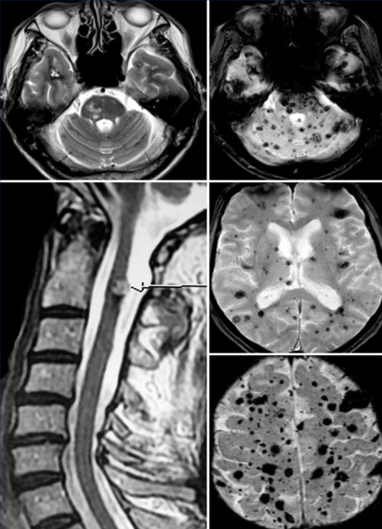

Кавернозные ангиомы - тема, которая почти всегда вызывает тревогу: на МРТ находят «сосудистое образование», и человек сразу думает про операцию или срочное лечение. На деле часто правильная тактика - спокойное наблюдение. Объясню простыми словами, чем кавернома отличается от АВМ и когда действительно нужно лечение. Кавернома (кавернозная ангиома) - это «клубочек» расширенных мелких сосудов, похожий на губку. Кровоток внутри него медленный. Именно поэтому каверномы часто ведут себя спокойно и годами никак не проявляются. Кавернома - это не опухоль. Это сосудистая особенность, которая у части людей обнаруживается случайно. 🌍Распространённость в популяции: 0,4–0,8% Этиология: •Спорадические — 80-90% случаев •Наследственные (аутосомно-доминантные) - до 20%, характеризуются множественностью. •Радио-индуцированные - очень редко (около 0,5%) Локализация: •Супратенториальные — 70–80% •Ствол головного мозга — 15–25% •Мозжечок, базальные ганглии и спинной мозг — около 5-10% Размеры: от малых (

Кавернома (кавернозная ангиома) - это «клубочек» расширенных мелких сосудов, похожий на губку. Кровоток внутри него медленный. Именно поэтому каверномы часто ведут себя спокойно и годами никак не проявляются.

Кавернома - это не опухоль. Это сосудистая особенность, которая у части людей обнаруживается случайно.

🌍Распространённость в популяции: 0,4–0,8%

•Наследственные (аутосомно-доминантные) - до 20%, характеризуются множественностью.

•Супратенториальные — 70–80%

•Ствол головного мозга — 15–25%

•Мозжечок, базальные ганглии и спинной мозг — около 5-10%

Размеры: от малых (1-2 мм) до гигантских (6 -7 см)